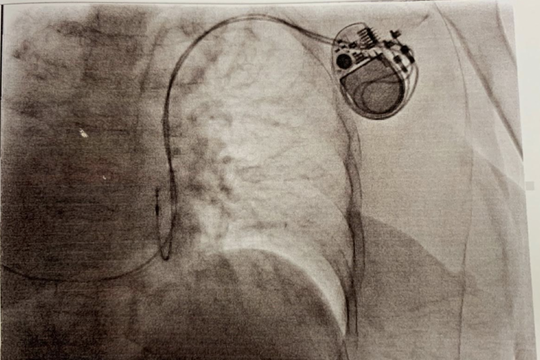

Ngừng tuần hoàn khi đi khám bệnh, nữ bệnh nhân Hải Phòng được cấp cứu kịp thời

Một nữ bệnh nhân 55 tuổi ở Hải Phòng đã ngừng tuần hoàn khi đi khám bệnh. Nhờ sự cấp cứu kịp thời của các bác sĩ Bệnh viện Việt Nam- Thụy Điển Uông Bí, bệnh nhân đã được cứu sống.

Cứu sống cụ bà có trái tim nằm bên phải, nguy kịch vì nhịp tim chậm

Nữ bệnh nhân nhập viện khi đột ngột choáng rồi ngất, tím tái và ngừng thở nguy kịch.